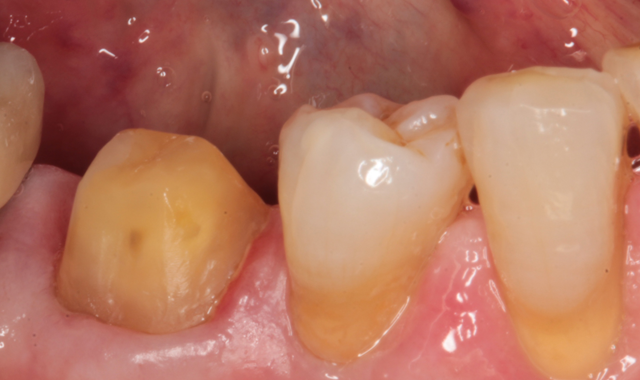

Figures 1 and 2 show the facial and occlusal views of a madibular molar that I prepared for a full crown.

Fig. 1 Fig. 2 Fig. 3